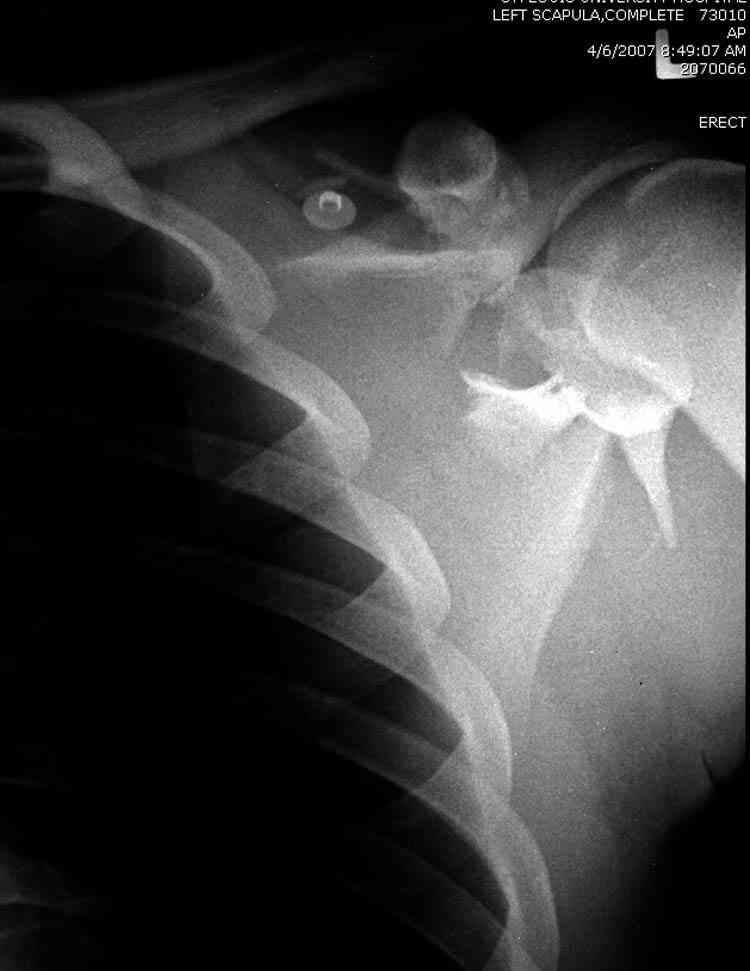

Если у вас имеется доказательство, что перелом лопатки изолированный, тогда нет необходимости операции, потому что стабильные изолированные переломы лопатки срастаются хорошо из-за хорошего кровоснабжения.

Для решения насчет оперативного вмещательства на лопатке сперва надо определиться с обьязательными ренгенологическими исследованиями, не менее трех стандартных проекций: прямая, аксиллярная и в позиции виде “Y”.

Прямую снимают под углом в 35 градусов от центра и вид “Y” в 90 градусов к нему. Несмотря на неудобства, больному необходимо сделать

аксиллярный снимок.

Нестабильные внесуставные переломы лопатки типично сочетаются с переломами ключицы и ребер.

При отсутствии соединения верхнего пояса с телом из-за перелома ключицы и шейки лопатки имеется состояние "floating shoulder", как в аналогии повреждения около коленного сустава "floating knee" при переломах костей выше и ниже коленного сустава.

В таких случаях, когда нет больших смещений на стороне суставной поверхности, и нет необходимости операции на лопатке, тогда ограничиваются фиксацией только ключицы, то есть фиксируется верхняя конечность к туловищу через ключицу...